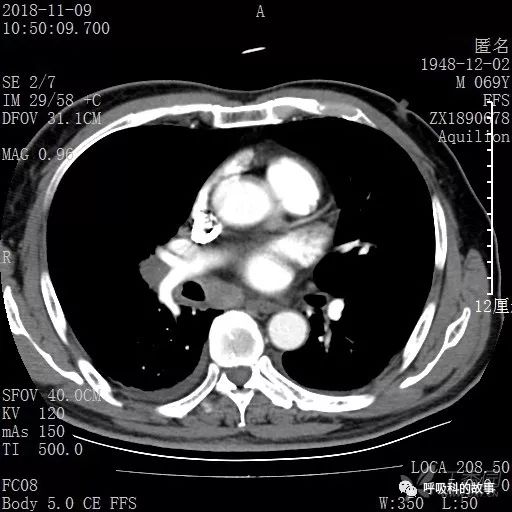

胸部增强CT示右肺门占位伴远端阻塞性肺炎,纵膈、右肺门、右侧颈根部、右侧腋下及肝门部肿大淋巴结。两侧胸腔少量积液。

纵隔窗的增强CT